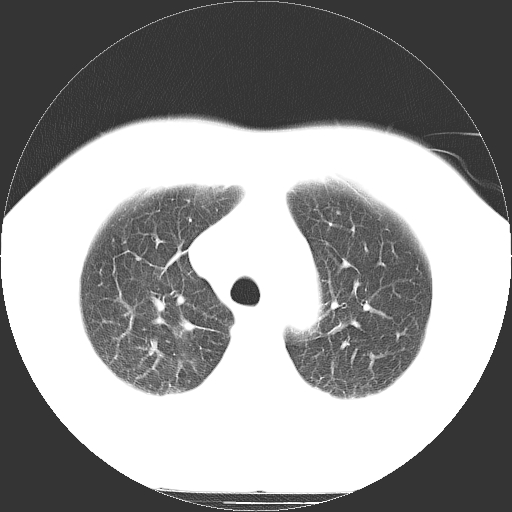

标题: CT21804:男,65岁,咳嗽、咳痰、发热5天。 [打印本页]

男,65岁,咳嗽、咳痰、发热5天。

慢支 肺间质纤维化合并感染!

考虑慢支并感染,肺间质纤维化。

两肺间质性炎症并感染

两肺间质纤维化,支扩合并感染,双侧胸腔积液